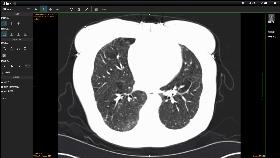

虽然X射线具有很强的穿透力,但是人体内有

些器官对X射线的吸收差别很小,X射线对

那些前后重叠组织的病变就难以发现

即使发现也难以确定病变发生在什么深度

CT的应用提供了理论依据,CT 技术

发展到今天,从最初的一个部位成像需要

几分钟,到现在的几秒、亚秒,甚至可以

对不断跳动的心脏进行「冻结」成像

可谓突飞猛进